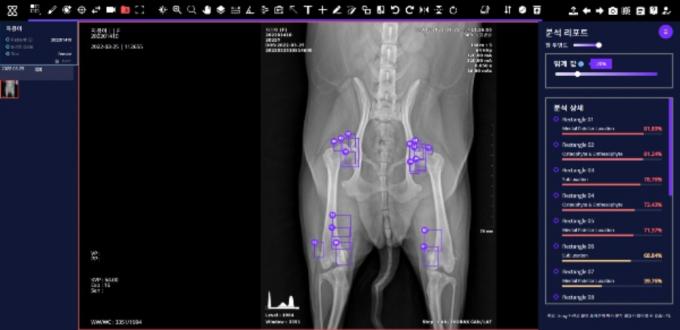

엑스칼리버는 병원에서 촬영한 반려견의 근골격(근골격계 질환 7종)과 흉부(흉부 질환 10종) 엑스레이 사진을 AI가 약 30초이내(인터넷속도 100Mbps 기준)에 분석해 수의사에게 제공하는 서비스다.

반려견의 엑스레이 사진을 AI플랫폼 '엑스칼리버 VET AI'에 업로드하면 AI가 비정상 소견 여부와 위치정보 등의 분석 결과를 수의사에게 알려주도록 돼 있다.

'엑스칼리버'의 질환탐지율(민감도)은 분야별로 84~97% 수준이다. 수의사들이 단시간에 판별이 어려운 질환도 시각화를 통해 빠르고 쉽게 찾을 수 있도록 돕는다.